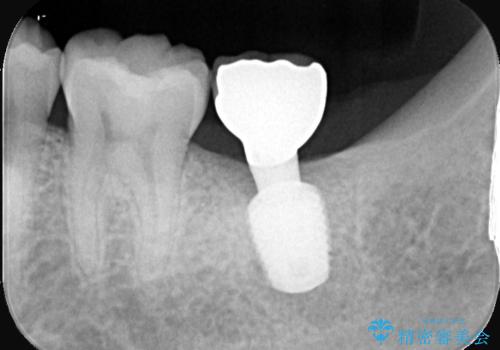

インプラントの上部構造(被せ物)には「スクリュータイプ」と「セメントタイプ」の2種類がありますが、セメントタイプは残留セメントが原因となり、インプラント周囲炎を引き起こす可能性があります。

そのため、当院では基本的に清掃性やメンテナンス性に優れたスクリュータイプを採用しております。